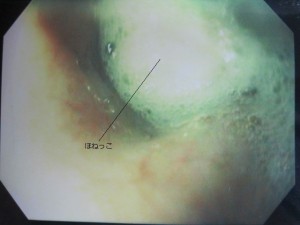

内視鏡で見た画像です。

食道内にほねっこがつまっています。